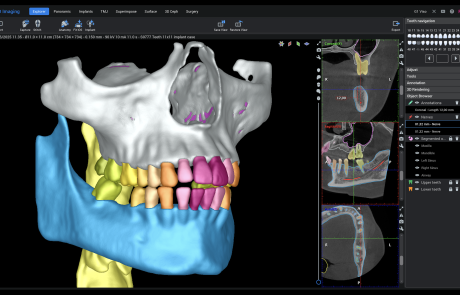

Viso G1

A powerhouse dental CBCT imaging unit covering volume sizes up to 11 x 11 cm.

With top-of-the-line 3D imaging technology and all the essential dental imaging programs, Planmeca Viso G1 is an X-ray device which easily meets every day dental imaging demands.

Why choose Planmeca Viso®? Planmeca Romexis®